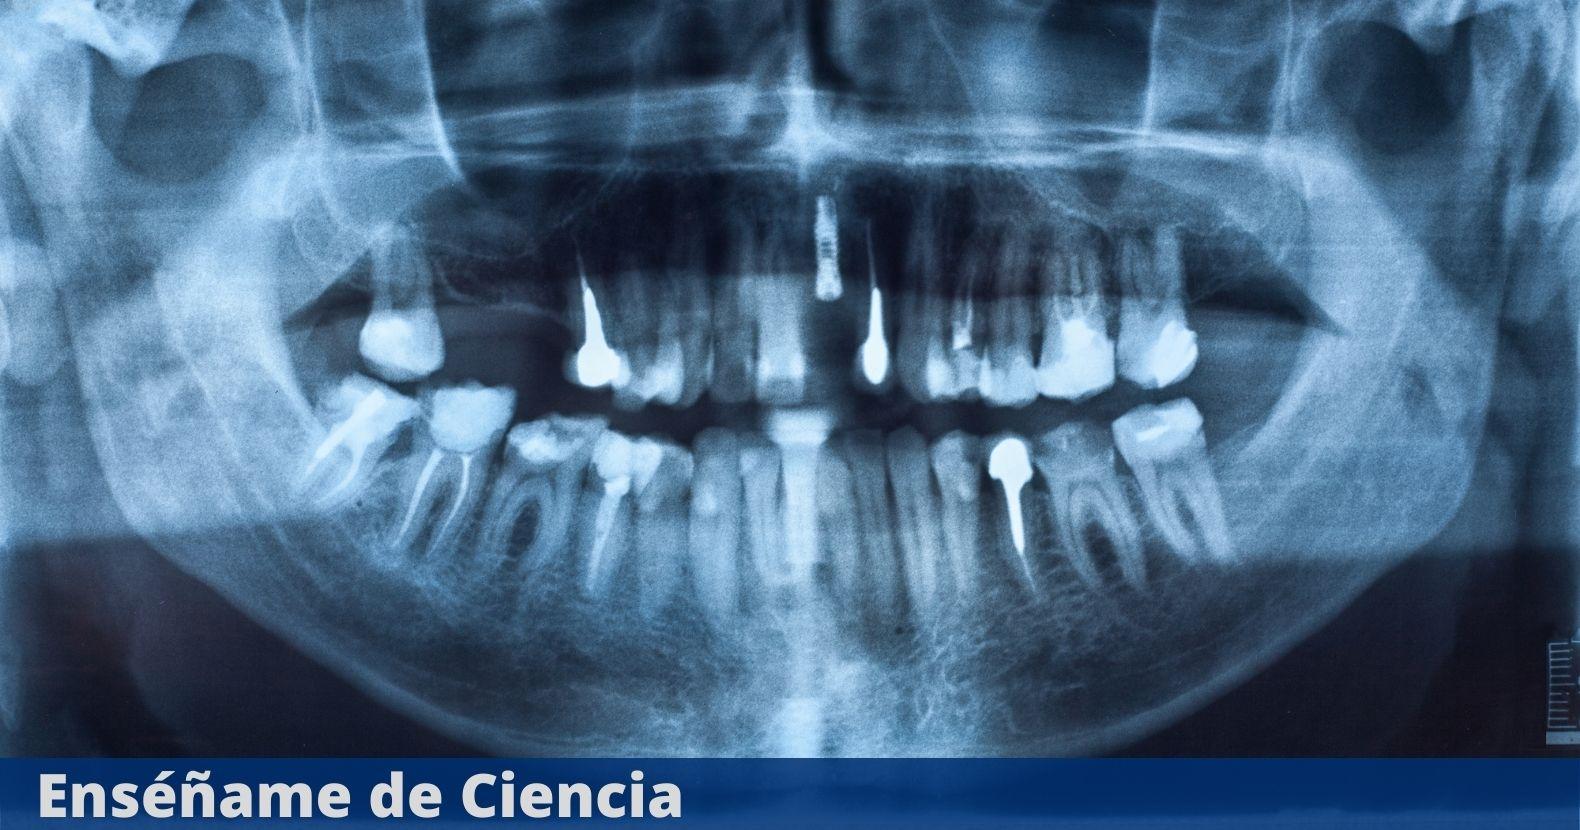

Ahora, los científicos dicen que tienen una de las pistas más definitivas hasta ahora para un culpable bacteriano detrás de la enfermedad de Alzheimer: la enfermedad de las encías.

En un artículo dirigido por Jan Potempa, autor principal y microbiólogo de la Universidad de Louisville, los investigadores informan sobre el descubrimiento de Porphyromonas gingivalis, el patógeno detrás de la periodontitis crónica (también conocida como enfermedad de las encías), en el cerebro de pacientes fallecidos de Alzheimer.

Ahora hay pruebas sólidas que conectan el patógeno intracelular gramnegativo, P. gingivalis y la enfermedad de Alzheimer. Además, el equipo identificó enzimas tóxicas llamadas gingipainas secretadas por las bacterias en los cerebros de los pacientes con Alzheimer, que se correlacionaban con dos marcadores separados de la enfermedad: la proteína Tau y la ubiquitina.

Pero aún más convincente, el equipo identificó estas gingipainas tóxicas en los cerebros de personas fallecidas que nunca fueron diagnosticadas con Alzheimer. Eso es importante, porque si bien P. gingivalis y la enfermedad se han relacionado antes, nunca se ha sabido si la enfermedad de las encías causa Alzheimer o si la demencia conduce a un cuidado bucal deficiente.